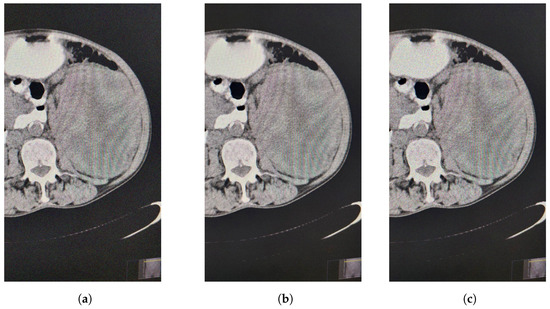

Let s p = 5 % (Figure 2).

The values of the metric of image quality UIQI for the filtered image (Figure 3a) by median filter are equal to U I Q I = 0.336147196 . The sharpness for the image filtered by VMF is 0.7578.

The tested values of the parameters appearing in those metrics ranged from 0 to 500 with a step of 100 for K , while t ranged from 0 to 1.1 with a step of 0.1. The best values of the UIQI image quality metric (for each color) for the image filtered (using the method proposed in [31]) were obtained for t = 0.5 and that is for K = 300 (Figure 3b),

U I Q I = 0.267224408 .

The sharpness for the image filtered by our metric is 0.9918.

Let s p = 20 % (Figure 2b).

The values of the metric of image quality UIQI for the filtered image by median filter are equal to U I Q I = 0.23954835 . The sharpness for the image filtered by VMF is 0.6943.

The tested values of the parameters appearing in those metrics ranged from 0 to 500 with a step of 100 for K , while t ranged from 0 to 500 with a step of 100. The best values of the UIQI image quality metric (for each color) for the image filtered were obtained for t = 400 and that is for K = 500 (Figure 3c),

U I Q I = 0.171202806 .

The sharpness for the image filtered by our metric is 0.9967.

Let s p = 50 % (Figure 2c).

The values of the metric of image quality UIQI for the filtered image by median filter are equal to U I Q I = 0.133346973 . The sharpness for the image filtered by VMF is 0.8719.

The tested values of the parameters appearing in those metrics ranged from 0 to 500 with a step of 100 for K , while t ranged from 0 to 500 with a step of 100. The best values of the UIQI image quality metric (for each color) for the image filtered were obtained for t = 500 and that is for K = 500 ,

U I Q I = 0.070832171 .

The sharpness for the image filtered by our metric is 0.9985.

Our results showed that our filtered image had slightly lower values in terms of UIQI image quality but significantly higher sharpness. This emphasizes the relationship between image quality and sharpness, which is crucial when preserving important details in the image.

Figure 3. (a) Decontaminated image by VMF. (b) Decontaminated image by FF. (c) Decontaminated image by FF.

Mathematics 12 02333 g003